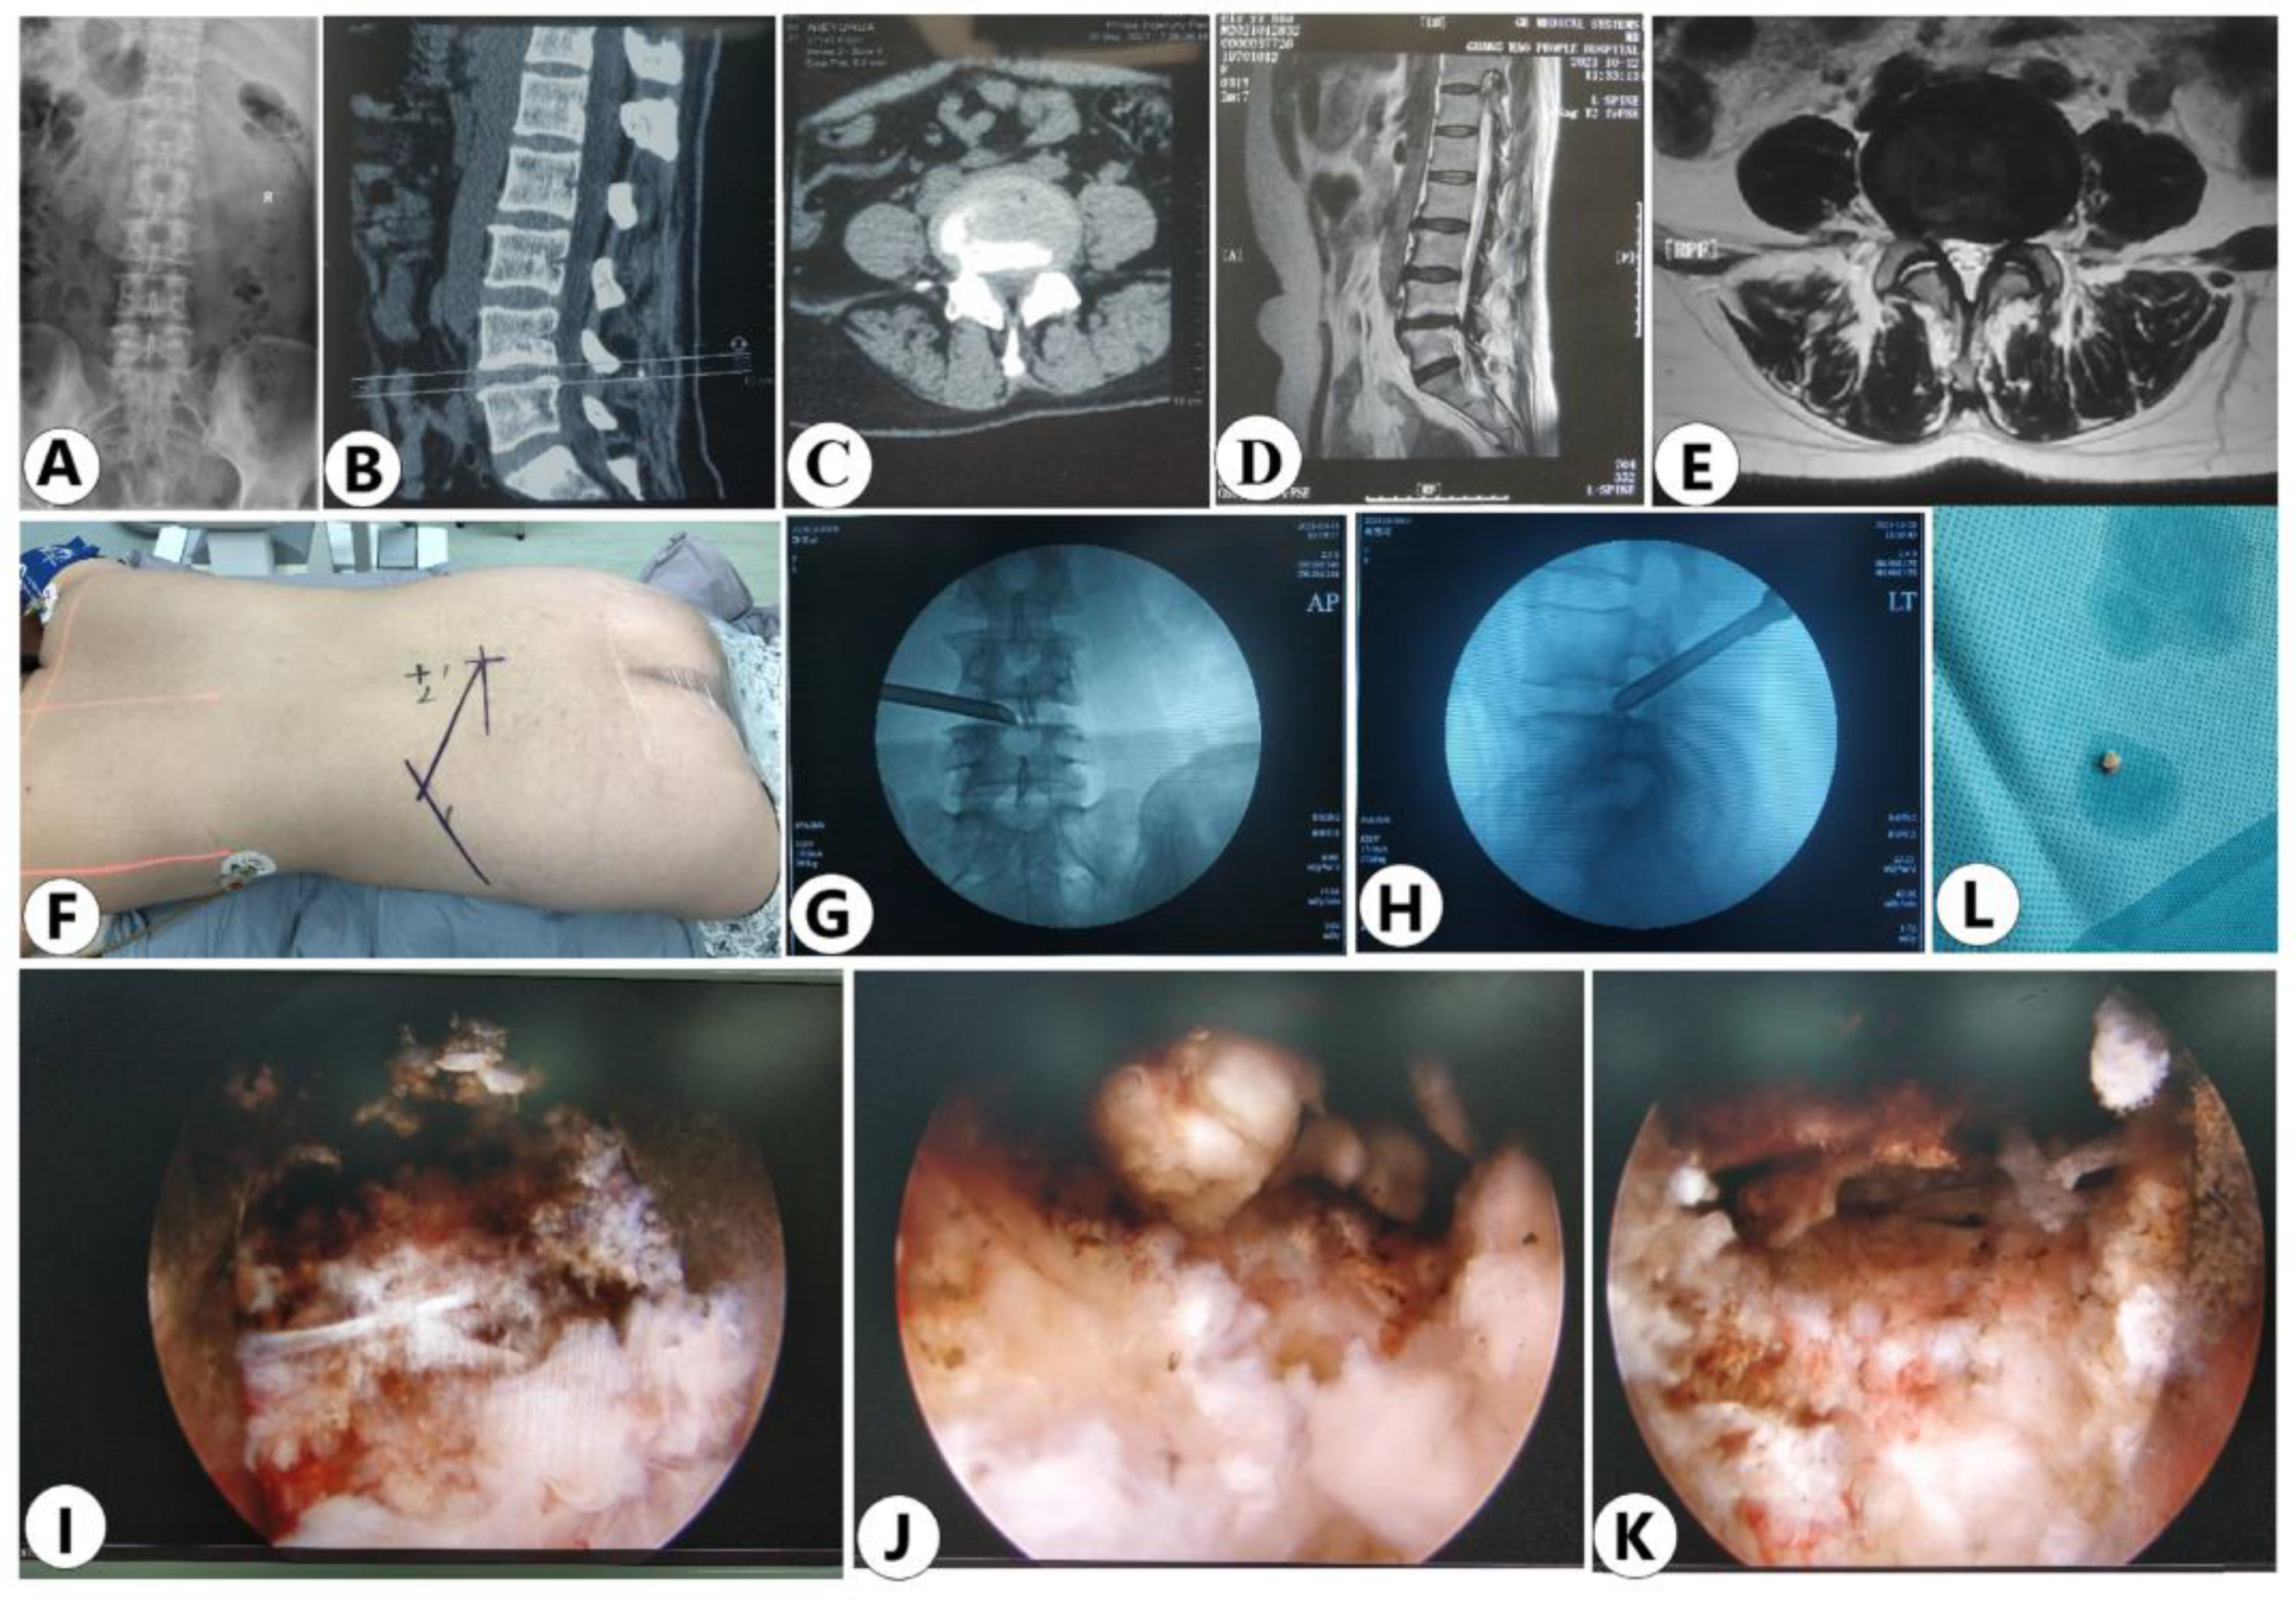

3.4. Case Presentation